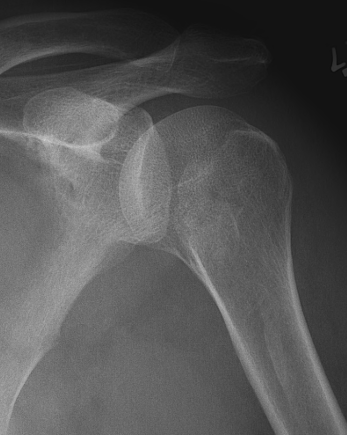

AP Xray

Abnormal overlap of humeral head on glenoid

Light-bulb sign - globular head secondary to internal rotation of the humeral head

Vacant Glenoid Cavity - > 6 mm space between humeral head and anterior rim of glenoid

Posterior shoulder dislocation

Posterior shoulder dislocations